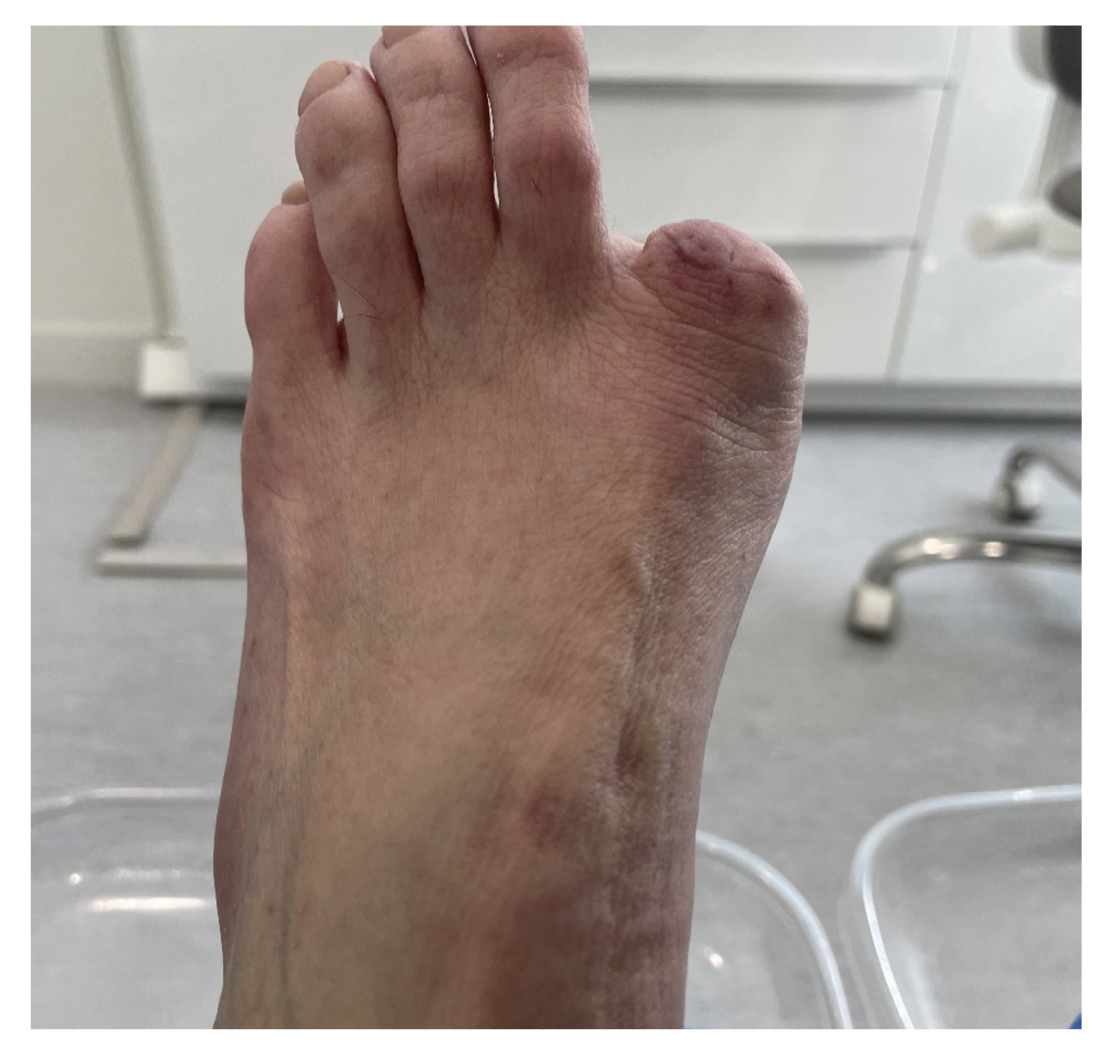

5 days postoperatively, the patient’s first dressing change was performed, which showed a good appearance and no local infection. The patient was explained the result of pathology and referred to the oncology service of her hospital, and from there to the dermatology and plastic surgery service where digital amputation was performed (Figure 10). Subsequent follow-up was conducted by the Oncology service for the next 6 months. After different tests, it was determined that no other treatment was needed. Figure 11 shows the timeline of the clinical case.

Figure 10. 30th week with digital amputation.